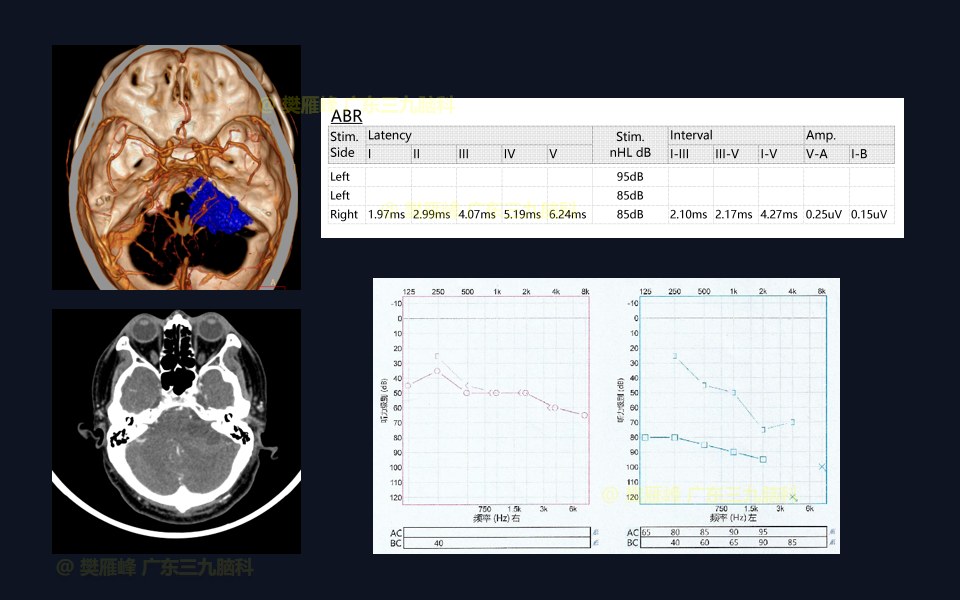

手术系列022:乙状窦后入路切除4级囊实性听神经瘤